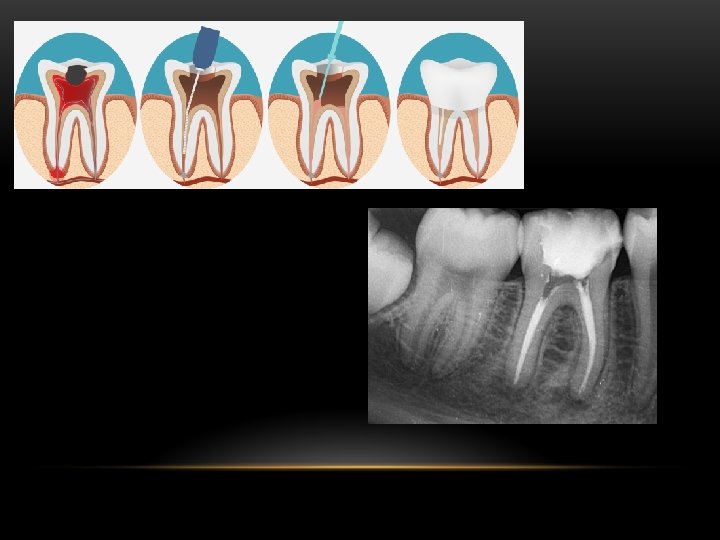

Endodoncia • Comprende la etiología, prevención, diagnóstico y tratamiento de las alteraciones patológicas de la pulpa dentaria y de sus repercusiones en la región periapical y por consiguiente en el organismo. Atiende la prevención y el tratamiento del endodonto y de la región apical y periapical. El endodonto comprende la dentina, la cavidad pulpar y la pulpa, mientras que la región apical y periapical comprende los tejidos de sustentación del diente. • La terapia endodóntica consiste en la extirpación parcial o la extirpación total de la pulpa dental. Se aplica en piezas dentales fracturadas, con caries profundas o lesionadas en su tejido pulpar (tejido conectivo laxo) en las que se da una sintomatología característica pulpitis.